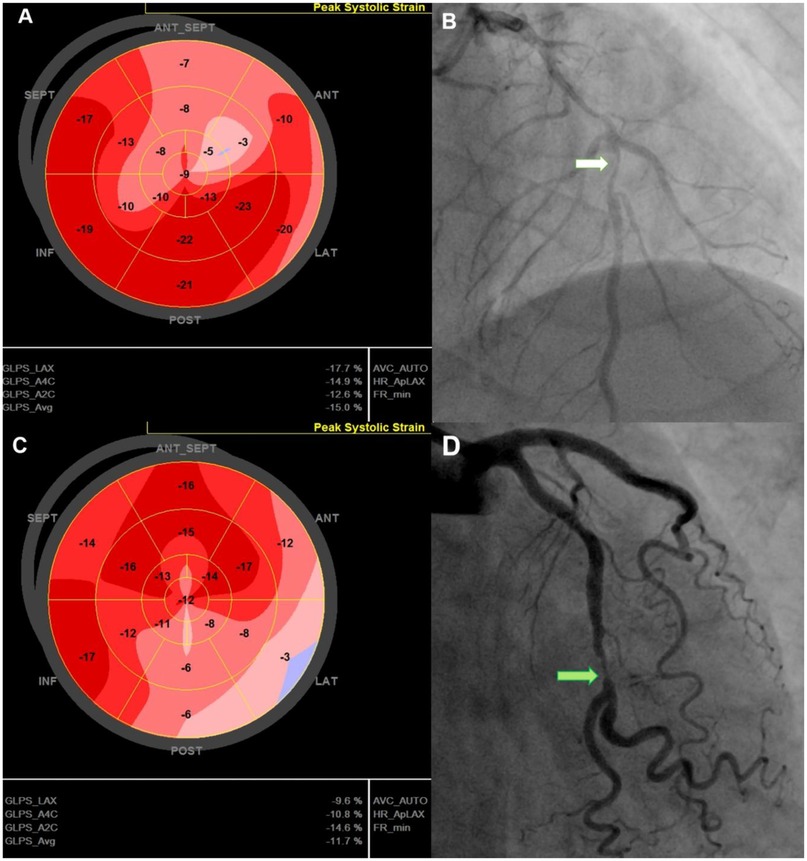

Findings on coronary angiography were recorded (Figure 1), including the culprit lesion, the number of diseased vessels, and lesion complexity as assessed by the SYNTAX (SYNergy between PCI with TAXUS™ and Cardiac Surgery) score. Additional biochemical workup included creatinine, peak high-sensitivity troponin T (hs-Troponin T), N-terminal pro-B-type natriuretic peptide (NT-proBNP) and complete blood count during the hospital stay.

The left ventricle was divided into 17 segments, covering the entire myocardium (25). Strain values were calculated by averaging the mean value in each segment (Figure 1). GCS and GRS were assessed from parasternal short-axis views at basal, mid, and apical levels. The short-axis region of interest was subdivided into six segments. The endocardium and epicardium were tracked manually. The anterior insertion point of the right ventricular free wall served as an anatomical landmark. The GCS and GRS were determined by averaging segmental-level measurements obtained from the same frames. All assessments were performed over three consecutive cardiac cycles and the results were averaged.

Representative cases illustrating GLS characteristics in post-PCI NSTE-ACS patients. 74-year-old man with a GLS of −15%, reduced longitudinal strain in the anterior septal region (A), EF of 51%, 90% stenosis of the LAD (white arrow)—(B), and no MACE during follow-up. 67-year-old man with a GLS of −11.7% with reduced strain in the lateral and posterior regions (C), LVEF of 52%, and 90% stenosis of the LCx (green arrow) (D); admitted for acute heart failure within 12-month follow up. GLS, Global Longitudinal Strain; LAD, left anterior descending (coronary artery); LCx, left circumflex (coronary artery); LVEF, left ventricular ejection fraction; MACE, major adverse cardiovascular events; PCI, percutaneous coronary intervention.